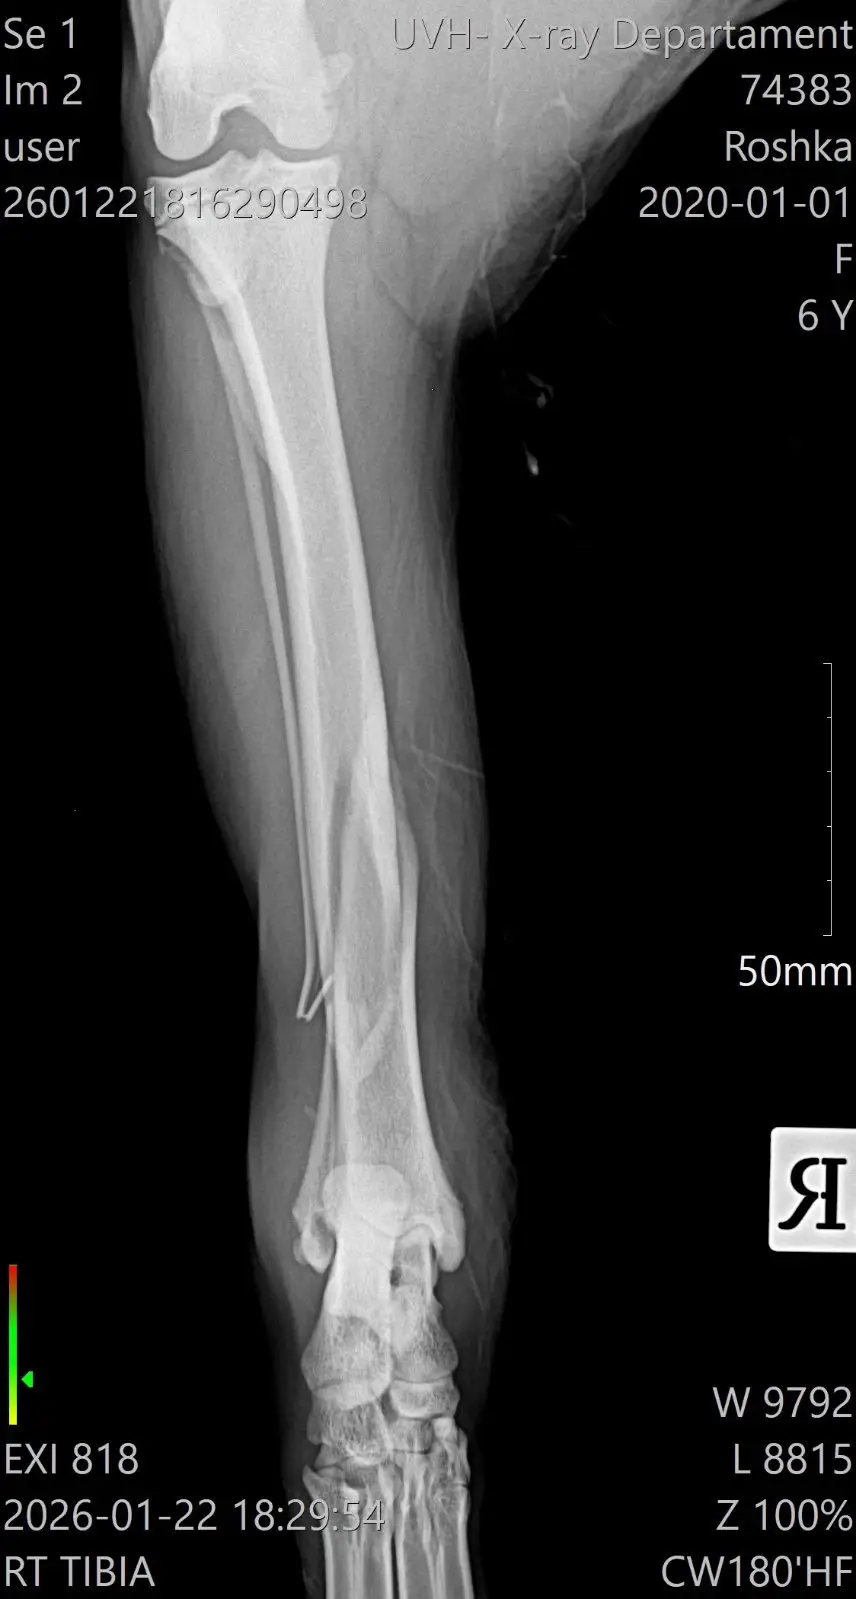

Защо Рошка има нужда от вас

Въпреки силата си, тя не може да се справи сама. Рошка се нуждае от спешни операции на задните краченца. За да може това 25-килограмово тяло да се изправи отново, са необходими импланти и винтове.